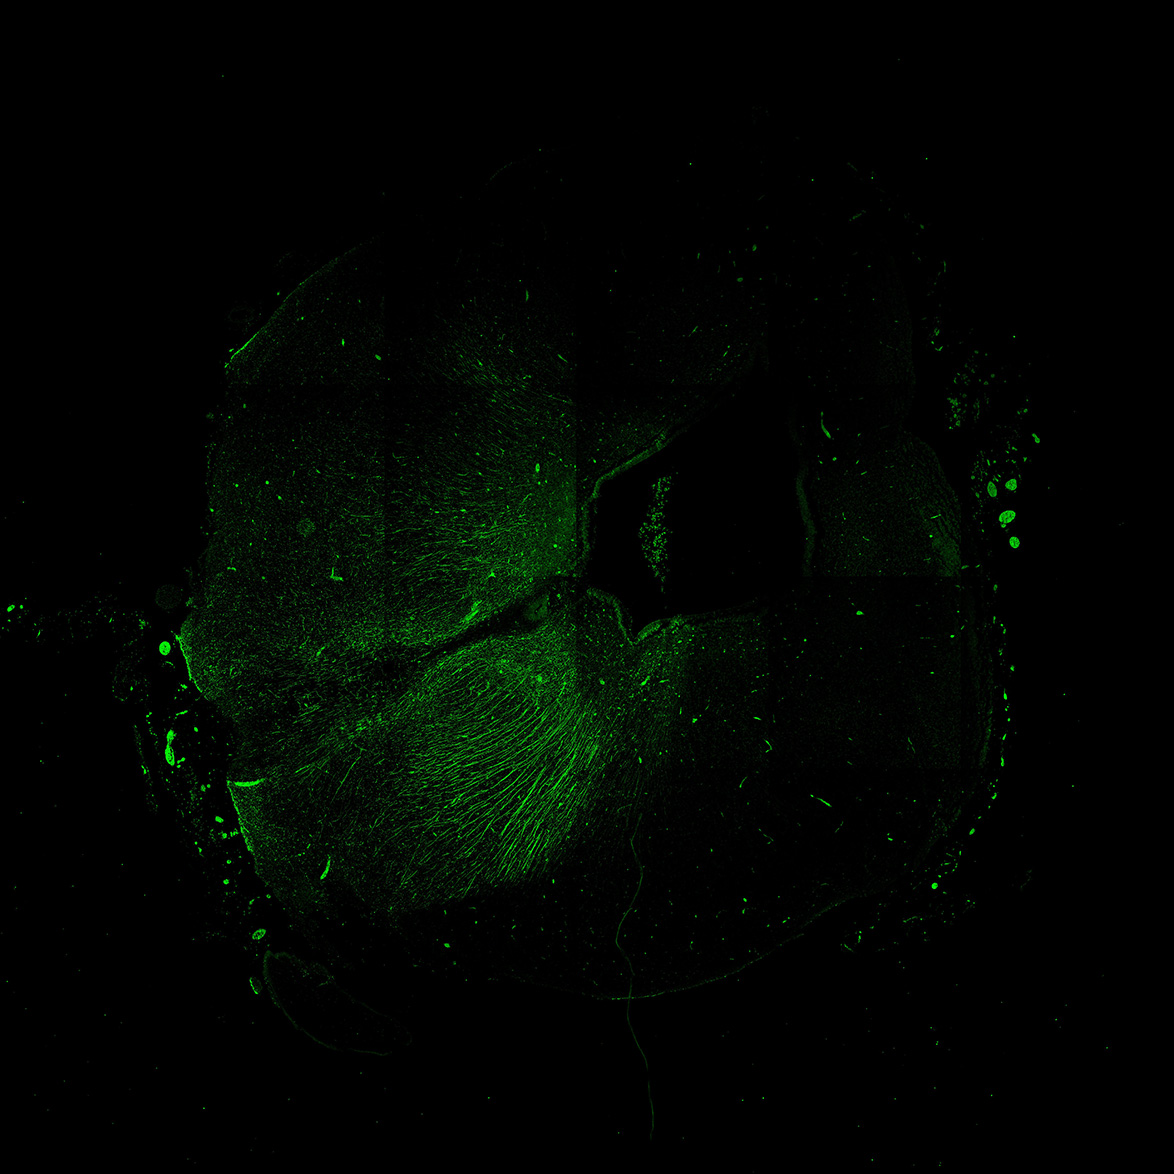

MAP2

6PCW human midbrain